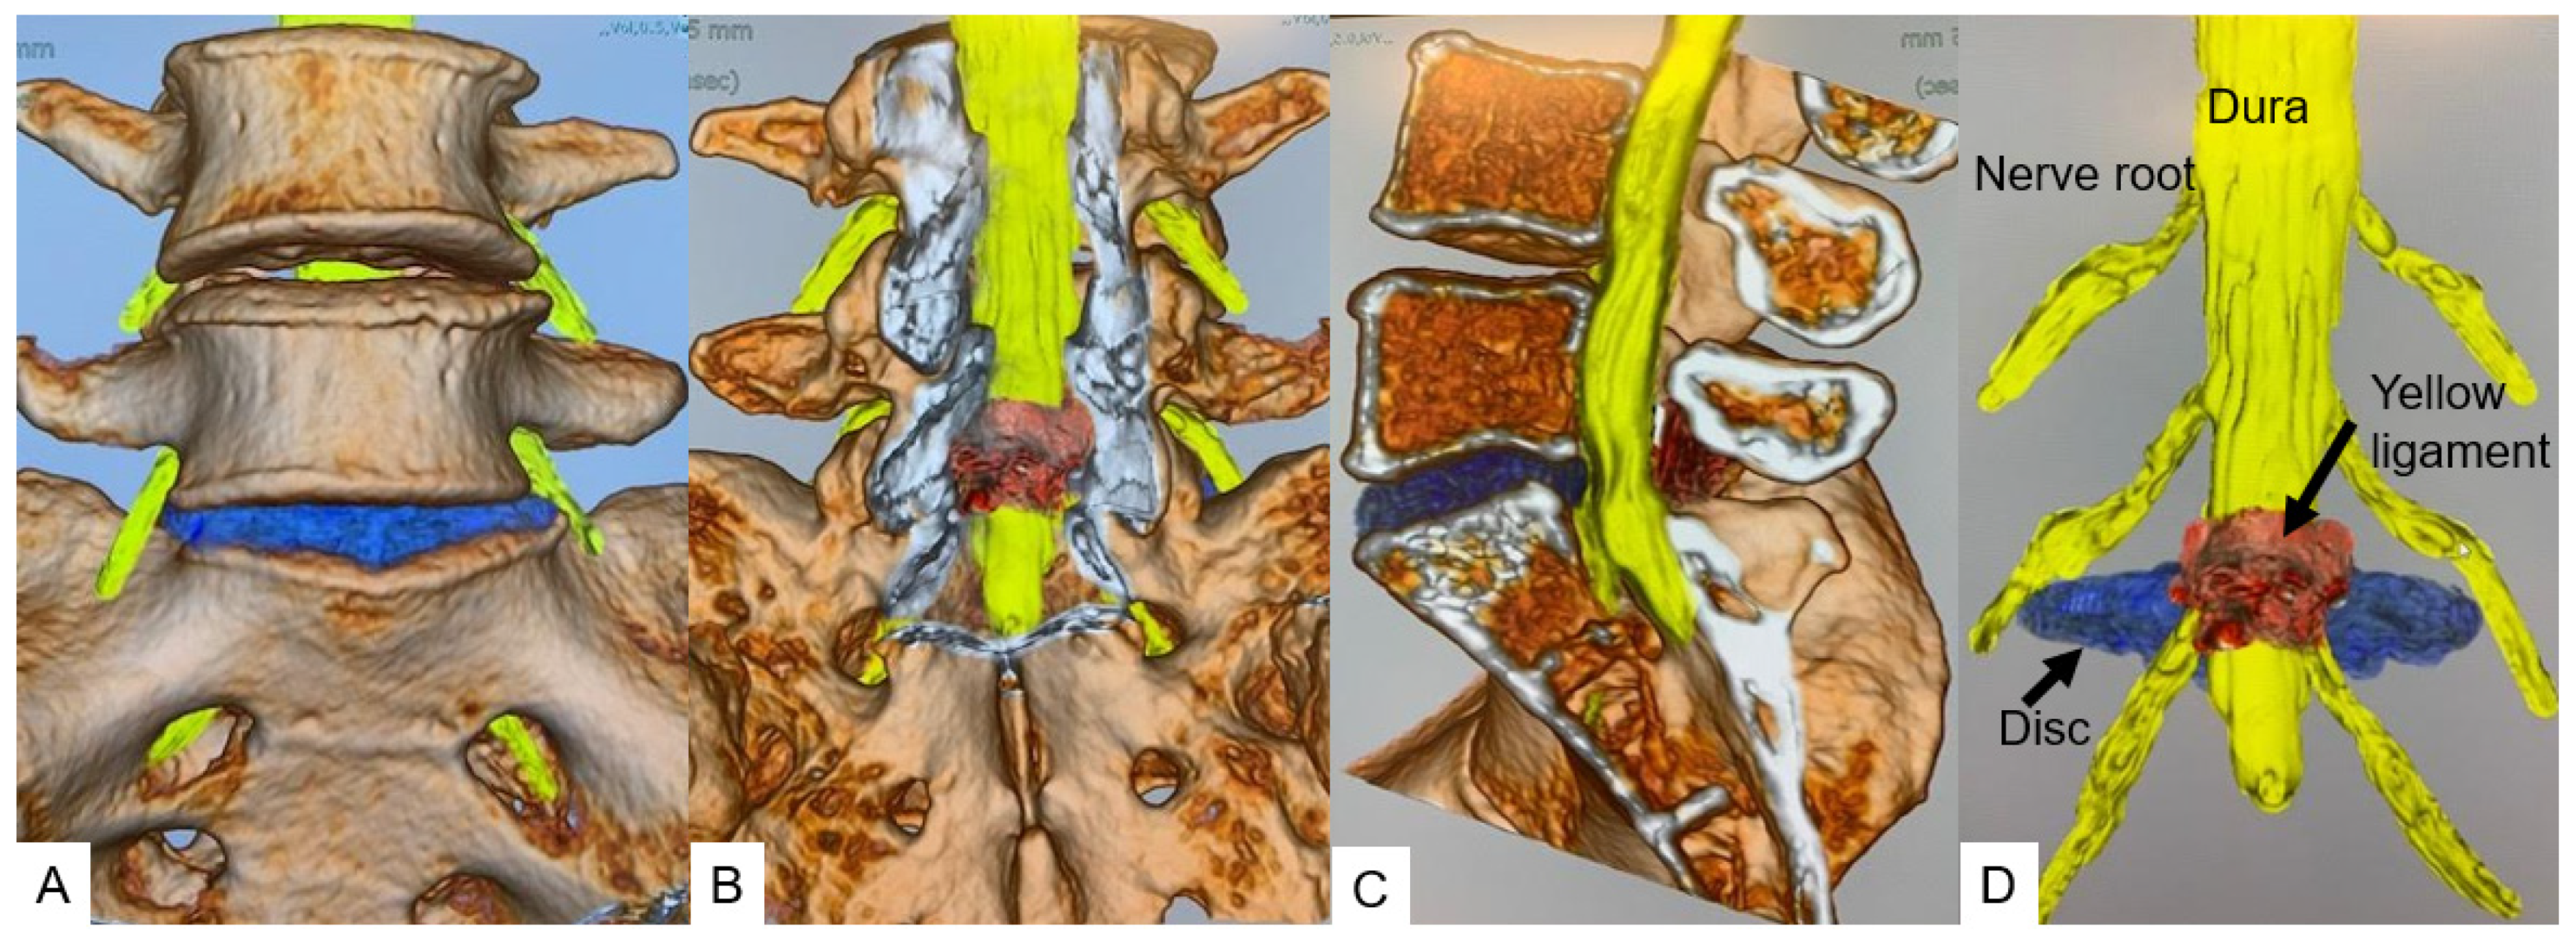

2.3. CT-MRI Fusion Image

2.4. Evaluation of Merged Images

3.5. Herniated Disc Visualization